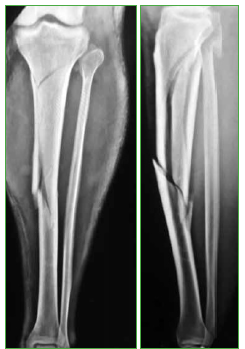

Materiales y Métodos: Se incluyó a 23 pacientes con un seguimiento posoperatorio mínimo de un año. Doce eran fracturas distales de tibia; 9, proximales y 2, segmentarias. Se evaluaron el rango de movilidad de la rodilla, el dolor posoperatorio con la escala de Lysholm, el eje posoperatorio y la tasa de consolidación.

Resultados: El arco de movilidad de la rodilla fue de 125° (rango 110-140). Al año de la cirugía, 16 de 23 pacientes no tenían dolor, 5 de 23 refirieron un leve dolor durante la actividad física y 2, dolores intensos durante la actividad física. En todos los casos, se consiguió un eje posoperatorio aceptable y la consolidación ósea. Un paciente requirió un aumento con una placa e injerto óseo.

Conclusión: La colocación de un clavo de tibia a través de un abordaje pararrotuliano medial con la rodilla en semiextensión es una técnica segura y simple para el tratamiento de las fracturas metafisarias de tibia.